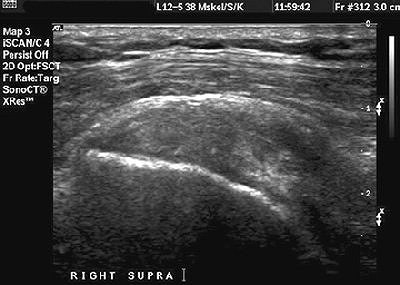

"Most rotator cuff tears occur at the site of insertion of the supraspinatus tendon in the greater tuberosity," Papatheodorou's group wrote. "Essential information for the orthopedic surgeon includes characterization of the tear, the dimensions and location of the tear, and the amount of tendon retraction on the longitudinal view."

Partial tears can occur in the supraspinatus tendon, the bursal side, and the articular side. For full thickness tears, the primary sign on ultrasound is a focal tendon defect or nonvisualization of the focal tendon. Secondary sonographic signs are bone irregularity of the greater tuberosity and the presence of fluid in the joint, they stated. Another sign is cartilage interface or uncovered cartilage.

![]() |

| Supraspinatus tendon, longitudinal view. The tendon demonstrates a heterogeneous echogenicity without any focal area representative of a tear. This pattern may indicate tendinosis or intrasubstance tear. Papatheodorou A, Ellinas P, Takis F, et al. US of the Shoulder: Rotator Cuff and Non-Rotator Cuff Disorders. RadioGraphics 2006;25:323. 10.1148/rg.e23. Published December 13, 2006. Accessed September 5, 2006. |